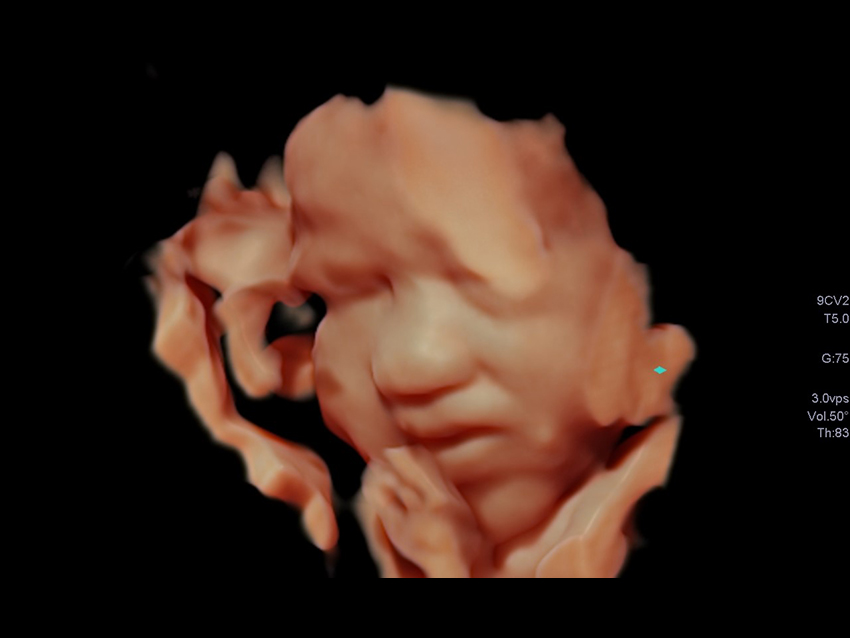

Удосконалені інструменти візуалізації, такі як 3D/4D luminance додають обличчю плода реалістичного вигляду.